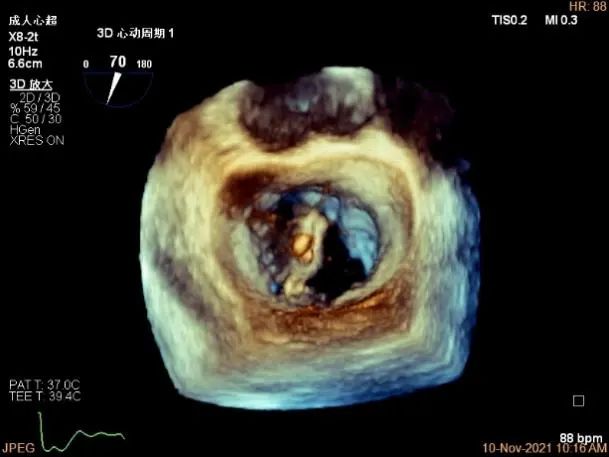

3D视图两个夹子近似并排排列,第二个夹子外侧小残余脱垂,瓣叶裂孔已不明显

二尖瓣瓣口平均跨瓣压差:5mmHg